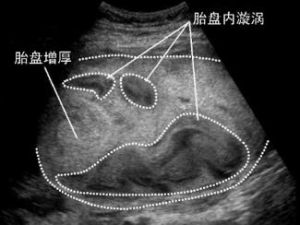

胎盤病變

胎盤異常

胎盤早剝

正常位置的胎盤,在胎兒娩出前,部分或全部從子宮壁剝離,稱胎盤早剝(placental abruption)。胎盤早剝和胎盤前置都是妊娠晚期流血的主要原因。